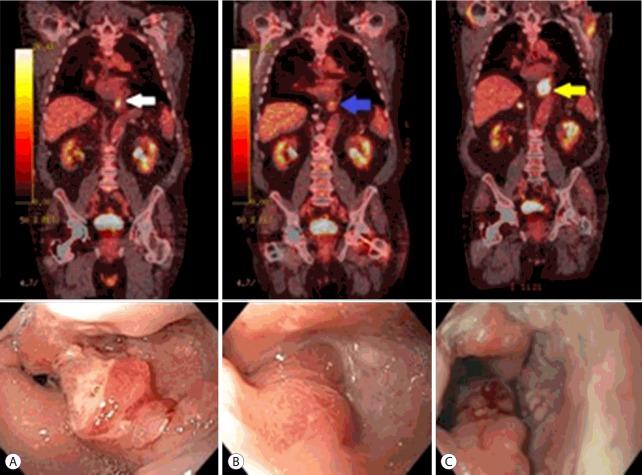

Esophageal cancer has a poor overall prognosis and is frequently diagnosed at a late stage. Conventional treatment for metastatic esophageal cancer involves chemotherapy and radiation. Local disease control plays a significant role in improving survival. Endoscopic spray cryotherapy is a novel modality that involves freezing and thawing to produce local ablation of malignant tissue via ischemic mechanisms. Spray cryotherapy has been shown to be effective, particularly for early T-stage, superficial esophageal adenocarcinomas. We present the case of a 72-year-old-male with locally recurrent stage IV esophageal adenocarcinoma and long-term survival of 7 years to date, with concurrent chemoradiation and serial cryoablation. He remains asymptomatic and continues to undergo chemotherapy and sequential cryoablation. The findings highlight the long-term safety and efficacy of cryotherapy in combination with chemoradiation, and suggest that cryoablation may have an additive role in the treatment of advanced stage esophageal adenocarcinoma.

食管癌的总体预后较差,且常于晚期被诊断出来。转移性食管癌的传统治疗方法包括化疗和放疗。局部疾病控制在提高生存率方面起着重要作用。内镜喷雾冷冻疗法是一种新型治疗方式,它通过冷冻和解冻,经由缺血机制对恶性组织进行局部消融。喷雾冷冻疗法已被证明是有效的,特别是对于早期T分期的浅表食管腺癌。我们报告了一例72岁男性患者,患有局部复发性IV期食管腺癌,至今已存活7年,采用同步放化疗和系列冷冻消融治疗。他仍无症状,继续接受化疗和序贯冷冻消融治疗。这些发现突出了冷冻疗法联合放化疗的长期安全性和有效性,并表明冷冻消融在晚期食管腺癌的治疗中可能具有辅助作用。